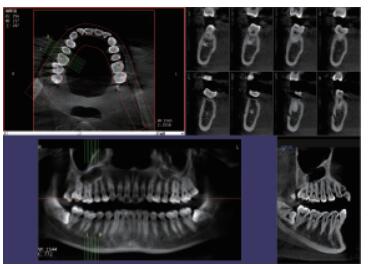

在口腔影像等細分領域,口腔CBCT的成像質量優于CT和普放。CBCT的X線利用率更高,且生成的圖像具備很高的各項同性空間分辨率。口腔CBCT能夠針對局部斷層曲面重建生成清晰無重疊的斷層影像以及3D影像,成像效果更好,有助于醫生的診斷,對于種植、綜合診斷、正畸等牙科診斷均有較大幫助??谇籆BCT技術優勢如下:

三維重建任意斷層

專有三維重建算法,可提供任意位置高清斷層影像。

高清口腔全景影像

通過三維容積影像,提取高清口腔全景影像。

多平面組合重建

可同時觀察軸向面、冠狀面和矢狀面圖像,方便臨床診斷。